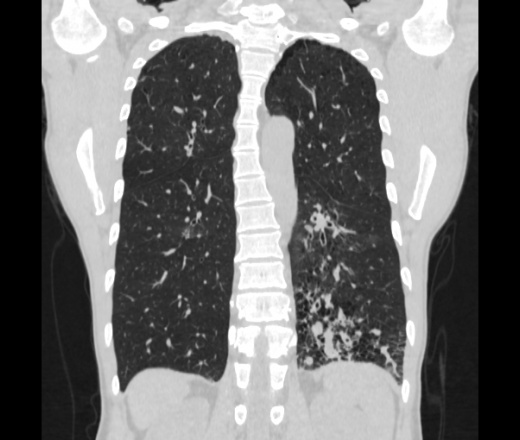

Мужчина пенсионного возраста. Цель назначения КТ ислючение зла в левом легком. Вижу тракционные бронхоэктазы с рубцовой эмфиземой по периферии, скорее всего БЭБ в стадии обострения. Дивертикулы трахеи. Выложил из за того что есть доля сомнения в отношении исключения зно3, немного смущают линии похожие на Керли.